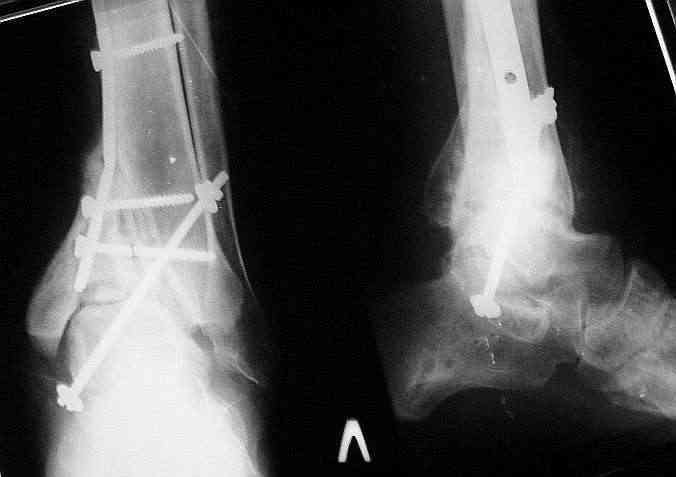

Было решено, уже по ходу операции, выполнить артродез болтом-стяжкой, тем самым компрессируя резецированные суставные поверхности и смещая стопу латерально, дабы нивелировать варусную деформацию и восстанавливая тем самым опорную ось всей конечности.

Послеоперационный период без особенностей.

Вчера (прошло около 8 месяцев)больной обратился ко мне в очередной раз с жалобами на боли умеренно-жгучего характера в области выстояния концов болта-стяжки. На момент осмотра:укорочение левой нижней конечности на 1,5 см; гипотрофия медиальной группы мышц голени и четырехглавой мышцы бедра; передвигается без дополнительной опоры в ортопедической обуви на растояние до 5 км; работает приемщиком цветных металлов (приходится перетаскивать грузы). Нарентгенограмме, насколько это можно видеть, костного блока сформировать не удалось, но движений в голеностопном суставе нет - ни активных, ни пассивных. Послеоперационные рубцы б/о; свищей и нагноения не было. Активно больногонаблюдать не приходилось, т.к. проживает в другом городе.